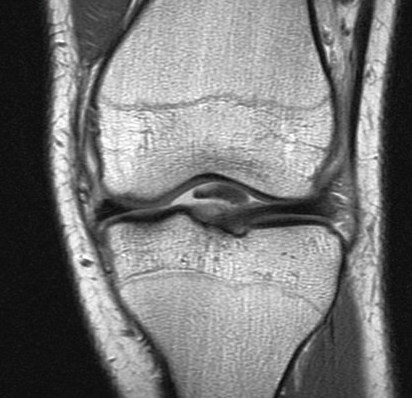

Figure 4 for case Unstable displaced lateral meniscus flap tear( RID2763 )

Figure 4

The flap is folded and displaced into the notch.

Unstable displaced lateral meniscus flap tear( RID2763 )